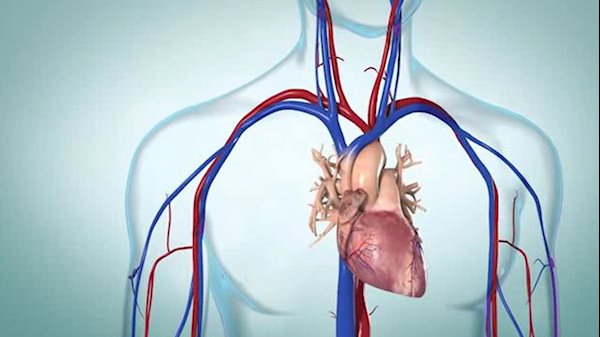

The heart is a muscle that pumps oxygen-rich blood to all parts of the body, so when you have heart failure, the heart is not able to pump as well as it should. Blood and fluid may back up into the lungs (congestive heart failure), and some parts of the body don’t get enough oxygen-rich blood to work normally.

Heart failure affects the body by interfering with the kidney's normal function of eliminating excess sodium and waste products. In congestive heart failure, the body retains more fluid, resulting in swelling of the ankles and legs. Fluid also collects in the lungs, which can cause shortness of breath, and these changes in the way the body handles fluid can also affect the kidneys and the liver.